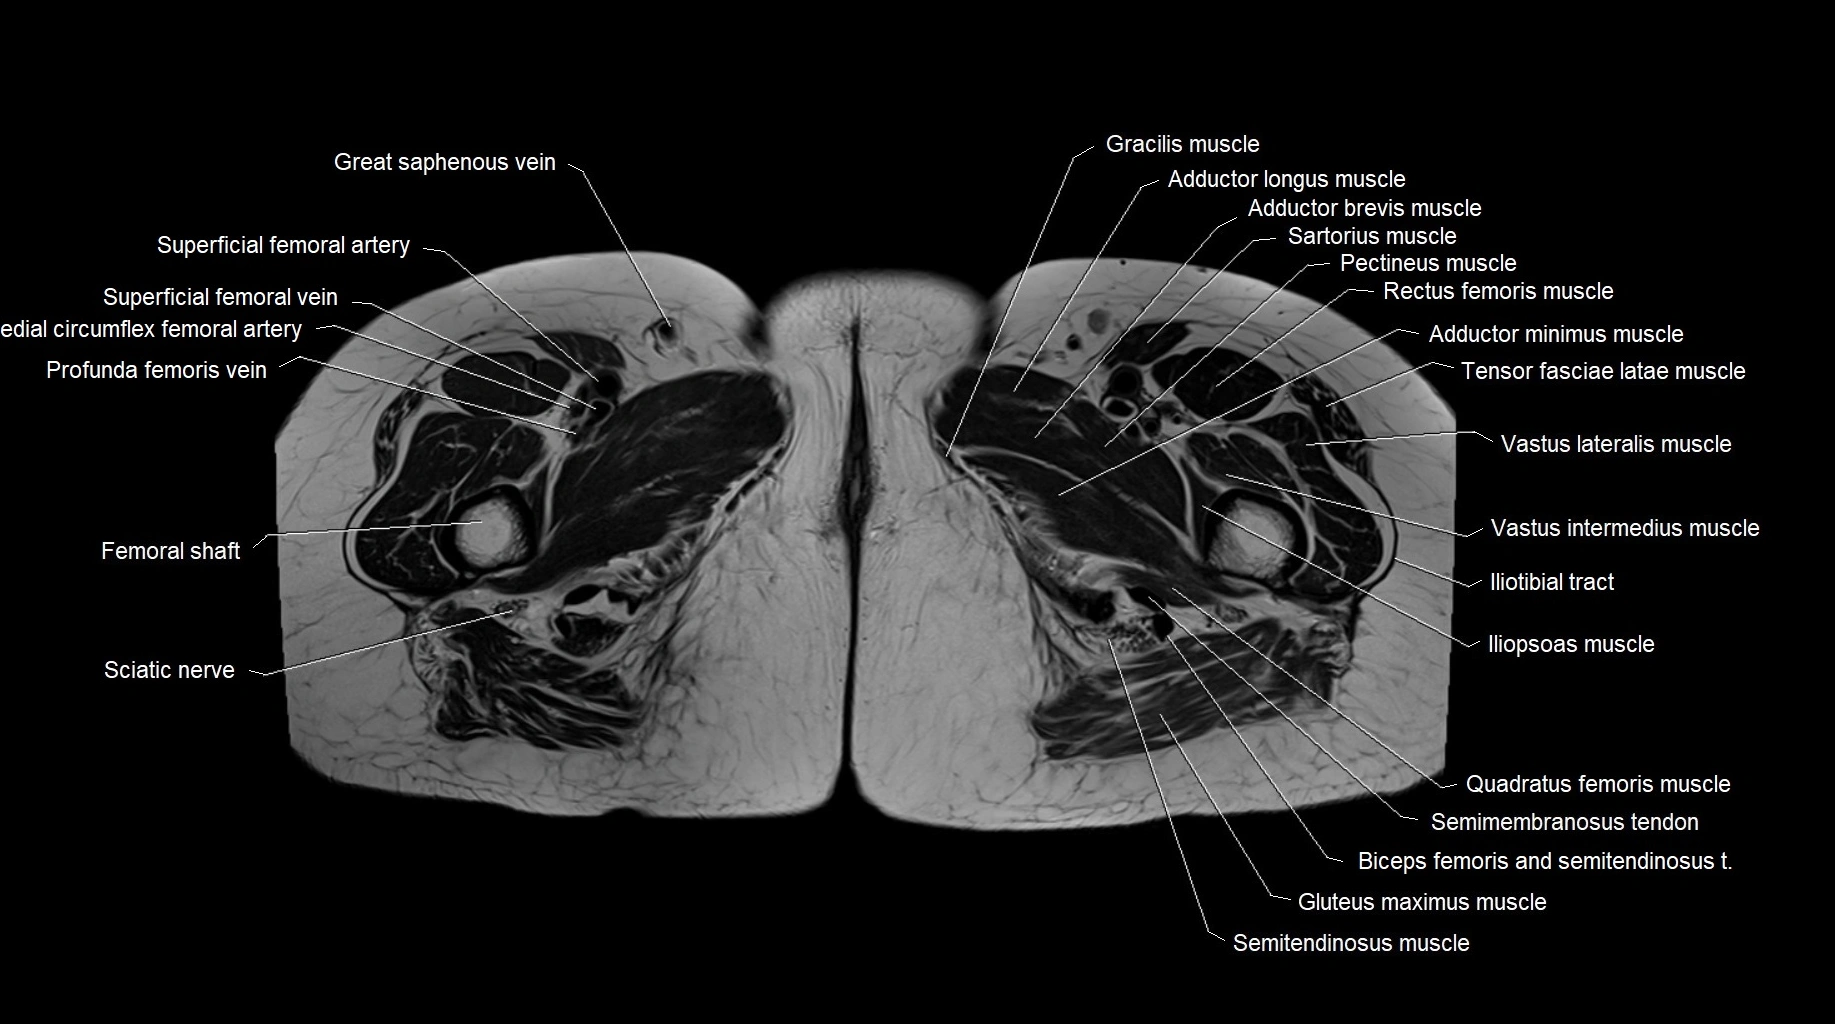

MRI images